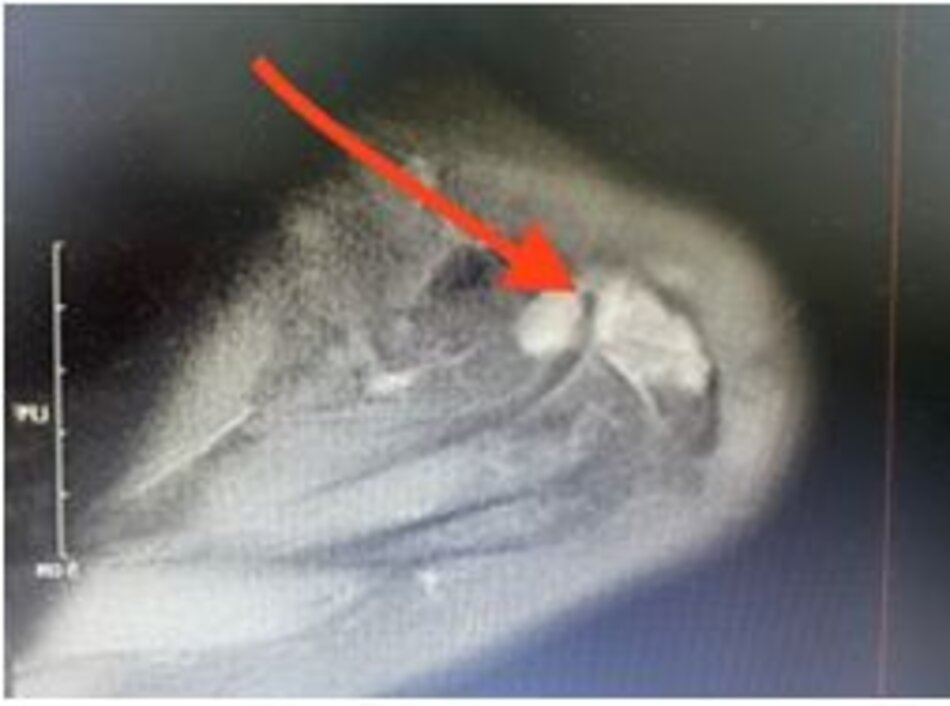

Viêm xương sụn lóc tách

Hình ảnh tổn thương viêm xương sụn lóc tách xương sên trên phim chụp MRI